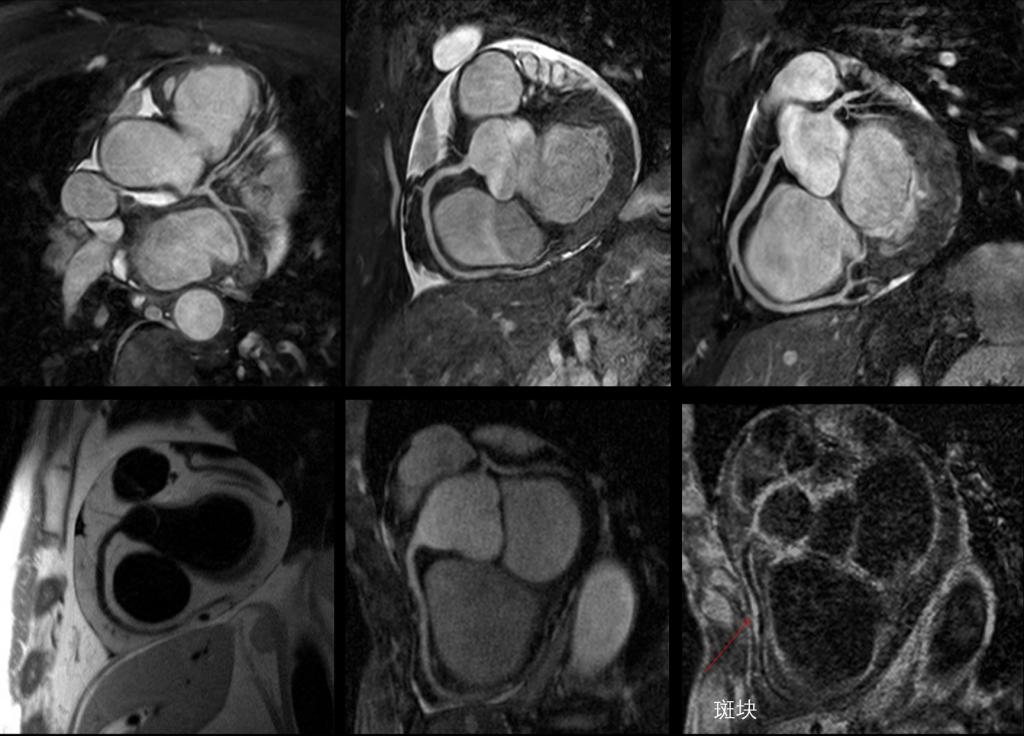

影像中心自成立以来,承担了科技部、国家自然科学基金委、卫生部、北京市科委等近百项国家和省部级项目,收到各种研究经费支持达5000万余元,已发表论文600余篇,发明专利60余项,国际专利10余项,培养学生130余人,获得各种奖励30余项。影像中心已成为全球重要的医学影像尤其是磁共振技术研发中心,开发出大视野高分辨血管壁多对比度成像、三维心肌定量成像、定量血流成像、定量生理成像、无变形高分辨率弥散成像等诸多原创技术,同时这些技术被广泛地应用在多项大规模临床人群队列研究当中形成了针对心脑血管、神经变性性疾病等原创性影像学解决方案。